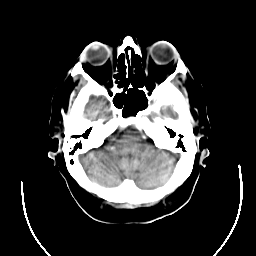

CT Study #3 -- Slice #6